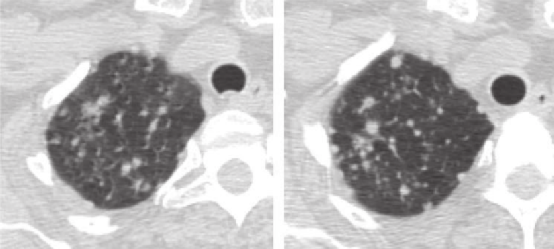

左肺上叶A、B,实性结节 (箭头)。左肺下叶C、D,亚实性结节 (箭头)。

与B和D相比,由于部分容积效应,A和C上的实性和亚实性结节边界显示较差。此外,D更好地显示出结节的实性成分。